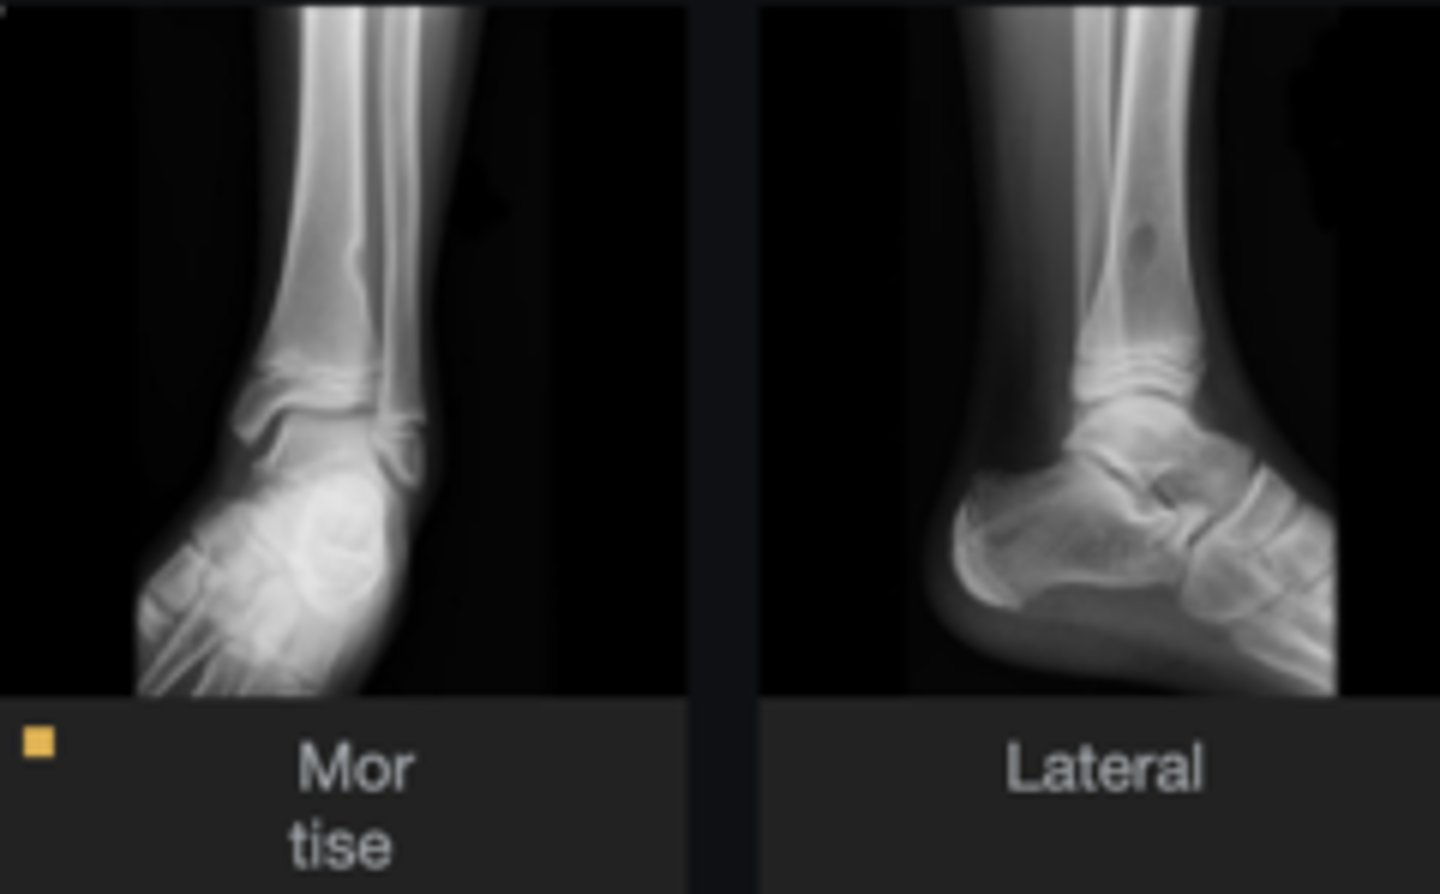

- Body of calcaneus

- Geographic

- Lucent

- Central target sequestrum

Describe the lesion

<p>Describe the lesion</p>

Intraosseous lipoma

Most likely diagnosis?

<p>Most likely diagnosis?</p>

Refer to orthopedist or specialist

Next step?

<p>Next step?</p>

Heel spur

What is going on with the posteroinferior calcaneus?

<p>What is going on with the posteroinferior calcaneus?</p>